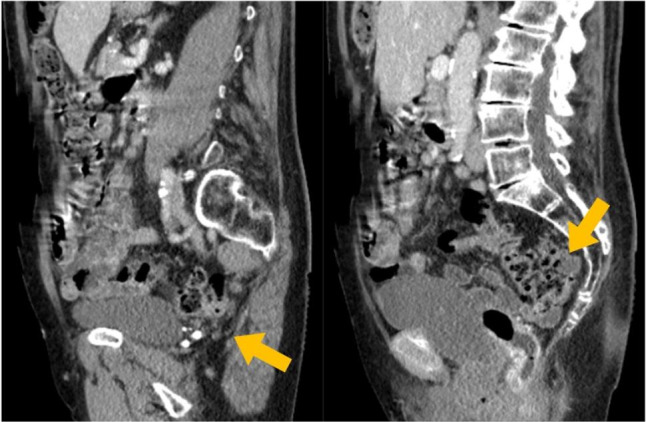

Materials and methods: In this video an 86-year-old woman with ODS and POP, suffering from a dolichocolon with rectal intussusception, an apical prolapse after total hysterectomy 1990, and occasional stress urinary incontinence underwent interdisciplinary laparoscopic surgery. A tubular anterior rectal and sigmoid resection with suture rectopexy as in a resection rectopexy (RRP) was combined with a sacrocolpopexy (SCP) using a synthetic mesh.

Abstract Image